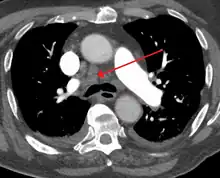

| Widened mediastinum | |

|---|---|

| Other names | Mediastinal widening |

![]() | |

| Widened mediastinum in a patient with achalasia | |

Widened mediastinum/mediastinal widening is where the mediastinum has a width greater than 6 cm on an upright PA chest X-ray or 8 cm on supine AP chest film.[11]

A widened mediastinum can be indicative of several pathologies:[12][13]